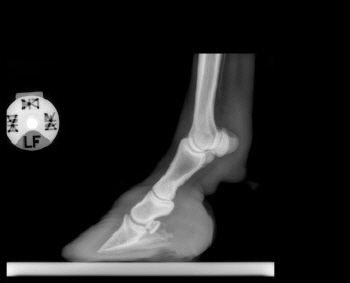

Röntgenbilder akuter- und chronischer Hufrehehufe vorher und nachher

Nachstehend stellen wir einige Röntgenbilder von Hufrehepferden ins Netz, welche das Vorher und das Nachher zeigen. Wir möchten damit aufzeigen, dass durch eine richtige Hufbearbeitung ein Hufbein wieder in eine korrekte Lage innerhalb der Hornkapsel zu liegen kommen kann.

In besonders schweren Fällen wurde doch zumindest eine Optimierung angestrebt.